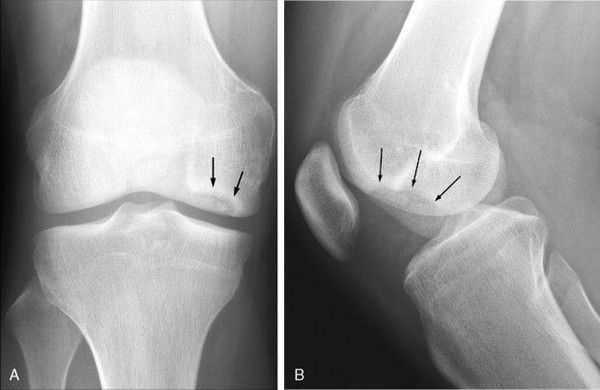

Диагностика деформирующегося артроза коленного сустава несложна. Многие авторы выделяют триаду основных рентгенологических признаков, которым сопутствует соответствующая клиническая картина: неравномерное сужение суставной щели, склероз (уплотнение) субхондральных пластинок, краевые костные разрастания в области эпифизов костей и заострение межмыщелковых возвышений.

I степень — это склероз субхондральных пластинок, заострение межмыщелковых возвышений, умеренные боли в суставе после физической нагрузки, нежный хруст при движениях в суставе.

II степень - клинически определяется деформация коленного сустава, периодически возникает синовит, боль по суставной щели, пальпируются костные образования по суставным поверхностям, хромота возникает после физической нагрузки или при длительной ходьбе. Рентгенологически определяется сужение суставной щели, склероз субхондральных пластинок, заострение межмыщелковых возвышений и значительные костные разрастания. У артистов балета костные разрастания раньше возникают на надколеннике.

III степень — самая тяжелая степень развития деформирующего артроза. Клинически отмечается ограничение подвижности в коленном суставе, боли как после физической нагрузки, так и в покое, деформация сустава, выраженный хруст. В этой стадии синовиты бывают уже реже и сустав почти «сухой». Отмечается атрофия мышц бедра. На рентгенограмме суставная щель узкая, массивные костные разрастания, дегенеративные кисты в субхондральной зоне, суставные поверхности резко деформированы, явления подвывиха в суставе.